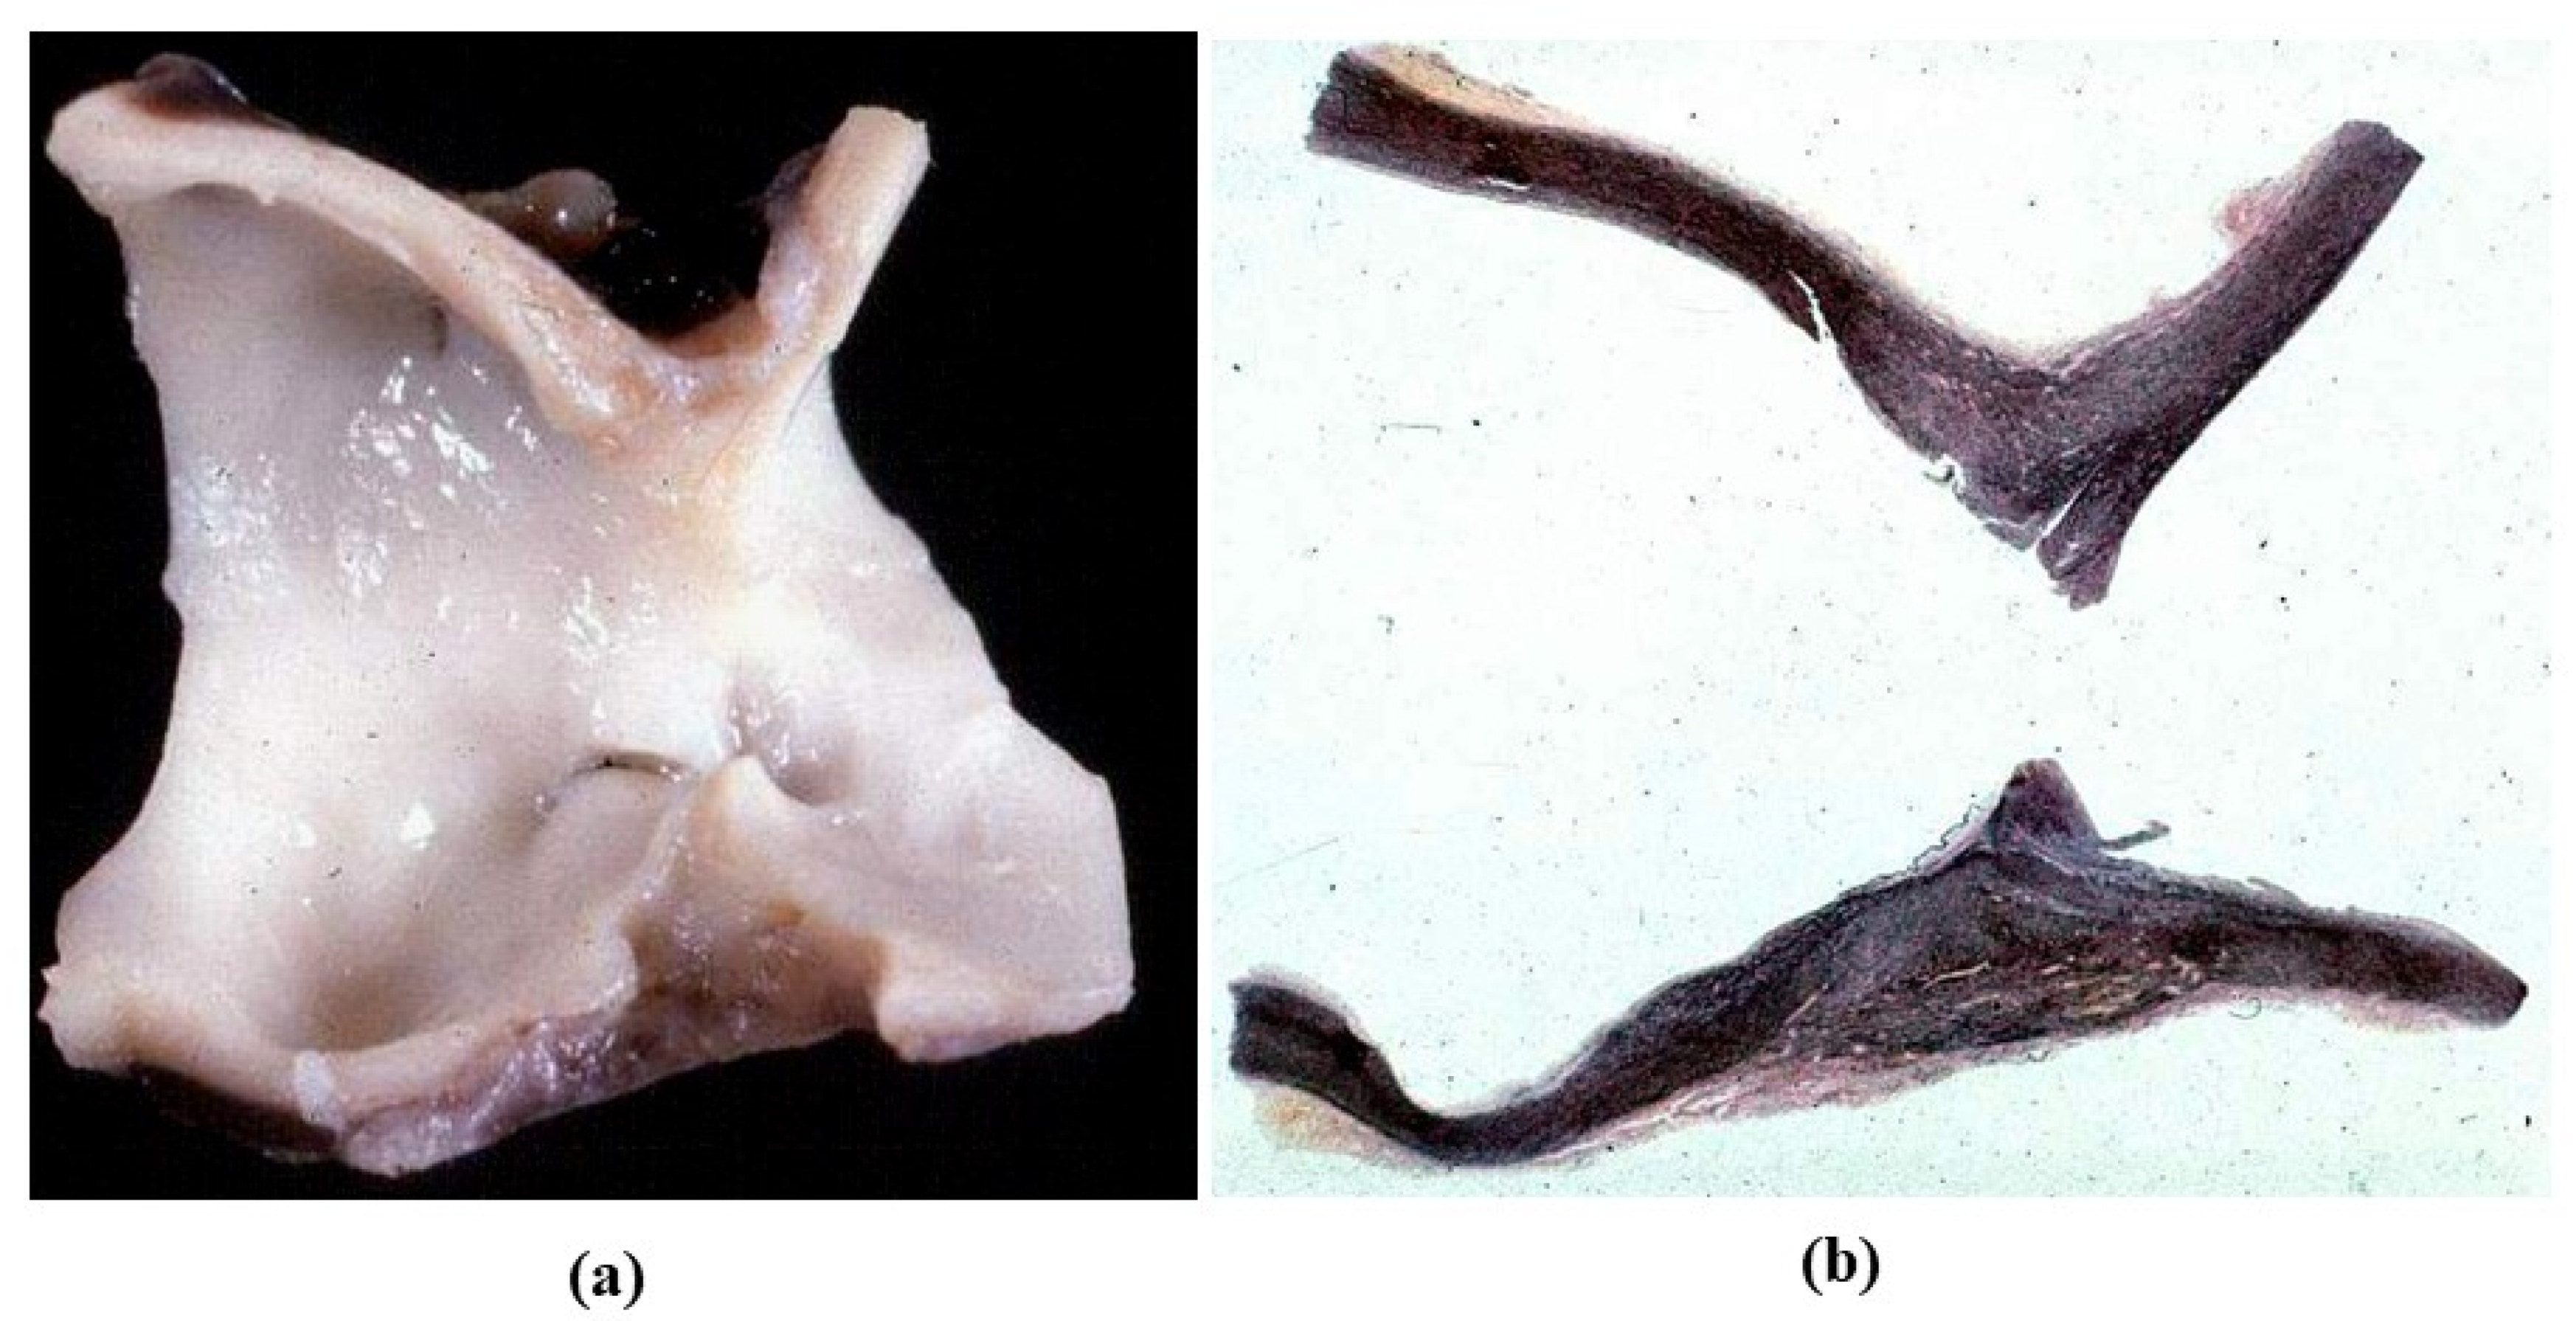

- The ultrastructure of the wall revealed that novel smooth muscle cells have immature aspects, with a central oval nucleus, few contractile filaments and focal densities mainly located close to cytoplasmic membrane and in the paranuclear region; repopulated cells of the cusps are scarcely differentiated cells, in some case showing short intercellular junctions, rough endoplasmic reticulum and focal basal lamina (Figure 33), whereas others exhibited a fibroblast-like morphology;

- The undifferentiated nature of the repopulated cells is demonstrated by colocalization of some biomarkers. Novel wall cells showed positivity both for α-SMA and vimentin and novel cusp cells for SMA, vWF, VEGF, VEGF R2, α-SMA and CD57 (HNK-1), which is a neural crest marker;